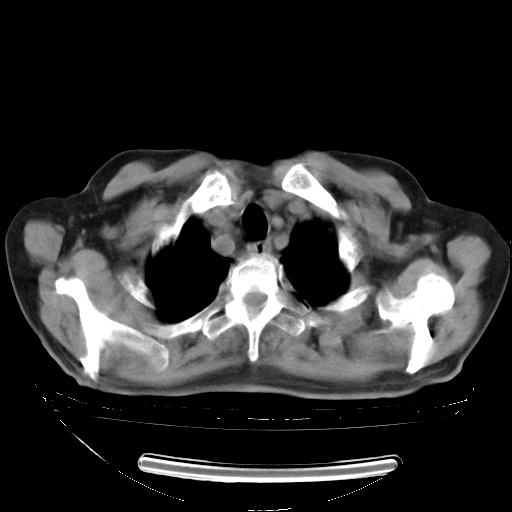

胸腹部CT,诊断意见:左上肺叶钙化灶、左侧胸膜局限性增厚并钙化、胆囊炎。描述部分肺组织呈磨玻璃样改变。

今天复查肺部CT,发现双肺广泛磨玻璃样改变。所以我把3月19日和5月9日相隔50天的肺部CT上传。请大家会诊。

2009年3月19日肺部CT片。

5月9日肺部CT(在4月27日齐鲁医院肺部CT描述部分肺组织磨玻璃样改变,12天后肺组织广泛磨玻璃样改变)